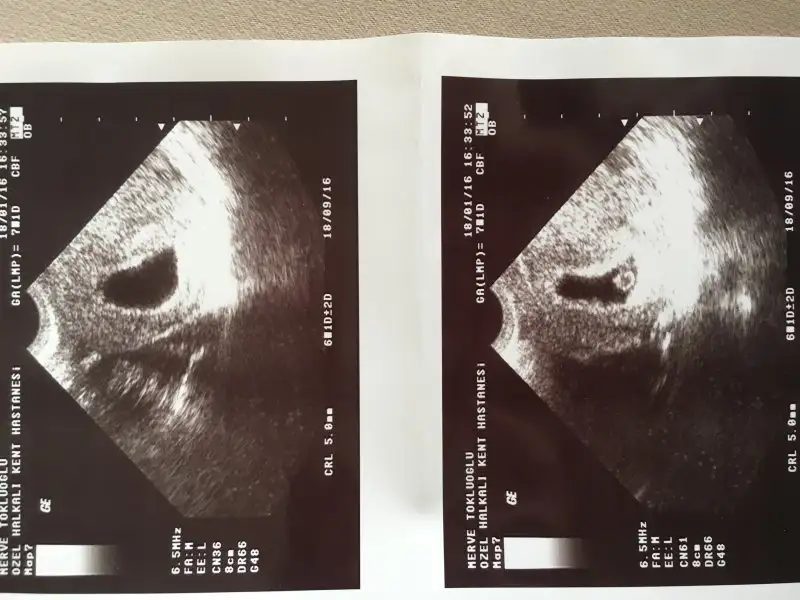

Hanımlar bunlar da benim yavrumun resimleri. İlki 6 haftalık sonraki 7 haftalık. Size zahmet tahmin edebilir misiniz bunu da?